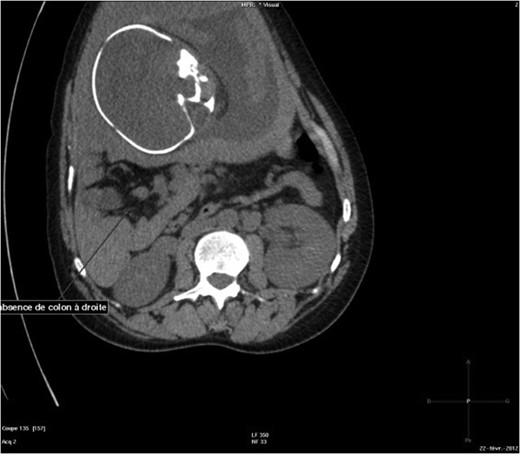

The abdominal-pelvic CT-scan showed a pre-splenic left position of the caecum and right colon, with no part of the colon on the right. The radiologist concluded that the patient was suffering from a complication of intestinal malrotation (IM) (Figs 1, 2, 3).

Abdominal-Pelvic CT-scan, non-contrast enhanced, in the sagittal plan, tenth dorsal vertebra level.